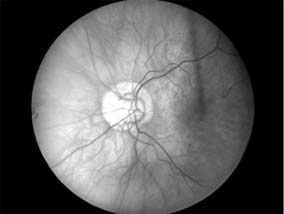

Primary optic nerve sheath meningioma is a rare tumor most commonly presenting, like other types of meningioma, in middle-aged women (Figure 14-19). Five percent of cases are bilateral. Visual loss is slowly progressive. The classic clinical features are a pale, slightly swollen optic disk with retinochoroidal collaterals, but in most cases the collateral vessels are not present (new window  Figure 14-6). Surgical excision invariably leads to complete loss of vision and is generally reserved for blind eyes to prevent intracranial spread of tumor. Focal radiotherapy is becoming more popular.

Figure 14-19

Figure 14-19: MRI of tubular optic nerve sheath meningioma.